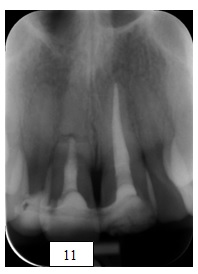

Rycina przedstawia kontrolne zdjęcie rentgenowskie wykonane w trakcie leczenia endodontycznego zęba 11 po urazie. Wskaż klasę wg Ellisa:

Pytanie 100